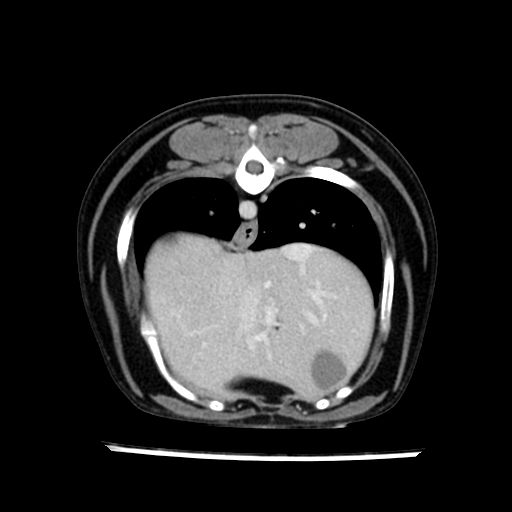

prescritto esame TAC

sequenza immagini limitata al fegato reni e surreni

le immagini ecografiche rispetto alla tac datano circa 7 mesi prima ,le surrenali sono normali nonostante il test acth sia risultato positivo .all’esame TAC dopo diversi mesi risultano aumentate armonicamente nel volume e si individua un forte sospetto di adenoma ipofisario .

sospetto adenoma ipofisario vs. meno probabilmente meningioma della base; intertiziopatia polmonare; lesione espansiva epatica, verosimilmente del lobo laterale sinistro, di sospetta natura neoplastica; lesioni spleniche di natura da definire; iperplasia/ipertrofia delle ghiandole surrenali, bilateralmente; vertebra di transizione del rachide toracico; tenosinovite cronica del muscolo bicipite brachiale di destra.

- Nessuna informazione diversa per quello che riguarda l’esame ecografico del fegato e la presa del contrasto si confermano le lesioni individuate e l’ipoenanchement in fase portale.

- la total body permette di escludere metastasi e di avvicinarsi all’interventistica

la tac dopo 7 mesi permette misure tridimensionali 5,2 x 9,2 x 4,5 cm (forma piu’ allungata )